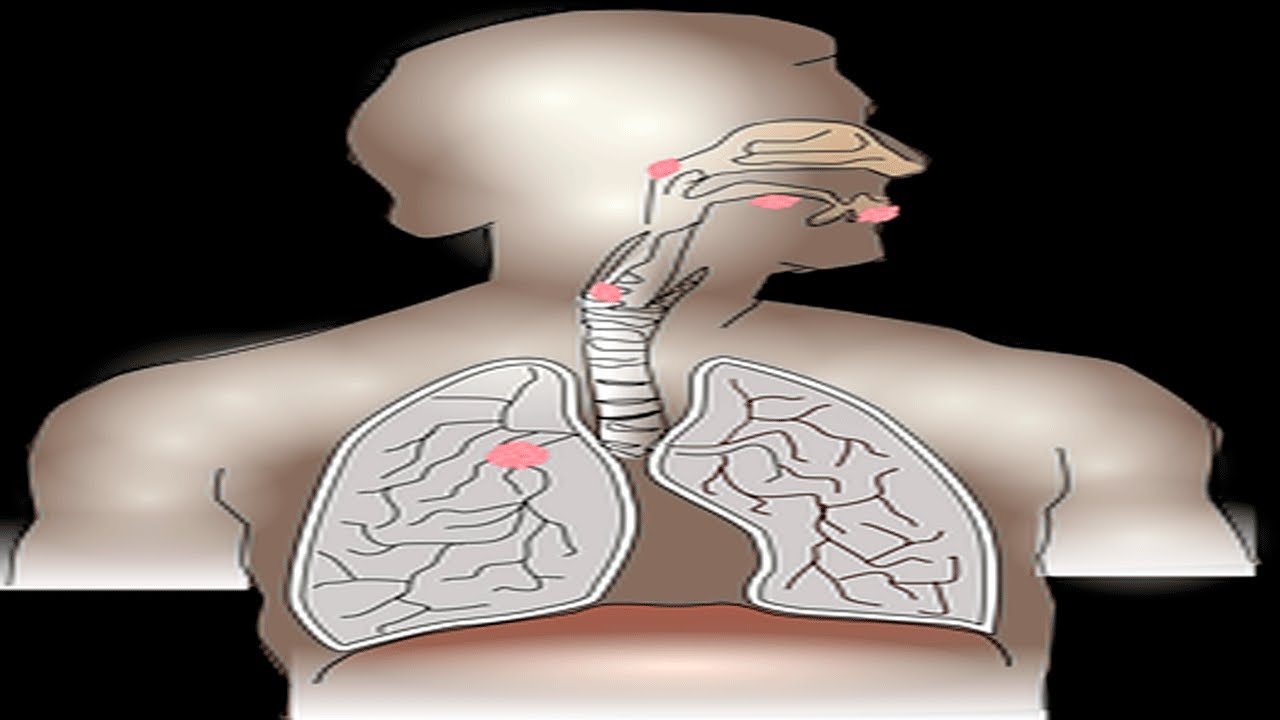

Las vías respiratorias son los conductos por los que el aire entra y sale de los pulmones. Cuando estas vías se obstruyen, puede resultar en dificultad para respirar. La obstrucción de las vías respiratorias puede ser causada por diversas condiciones médicas o factores externos. Es importante poder identificar los signos de una posible obstrucción para actuar rápidamente.

Las obstrucciones en las vías respiratorias pueden ser causadas por diferentes factores. Desde cuerpos extraños que se inhalan accidentalmente hasta condiciones médicas como el asma, la enfermedad pulmonar obstructiva crónica (EPOC) o la bronquitis crónica, existen diversas razones por las cuales las vías respiratorias pueden obstruirse.